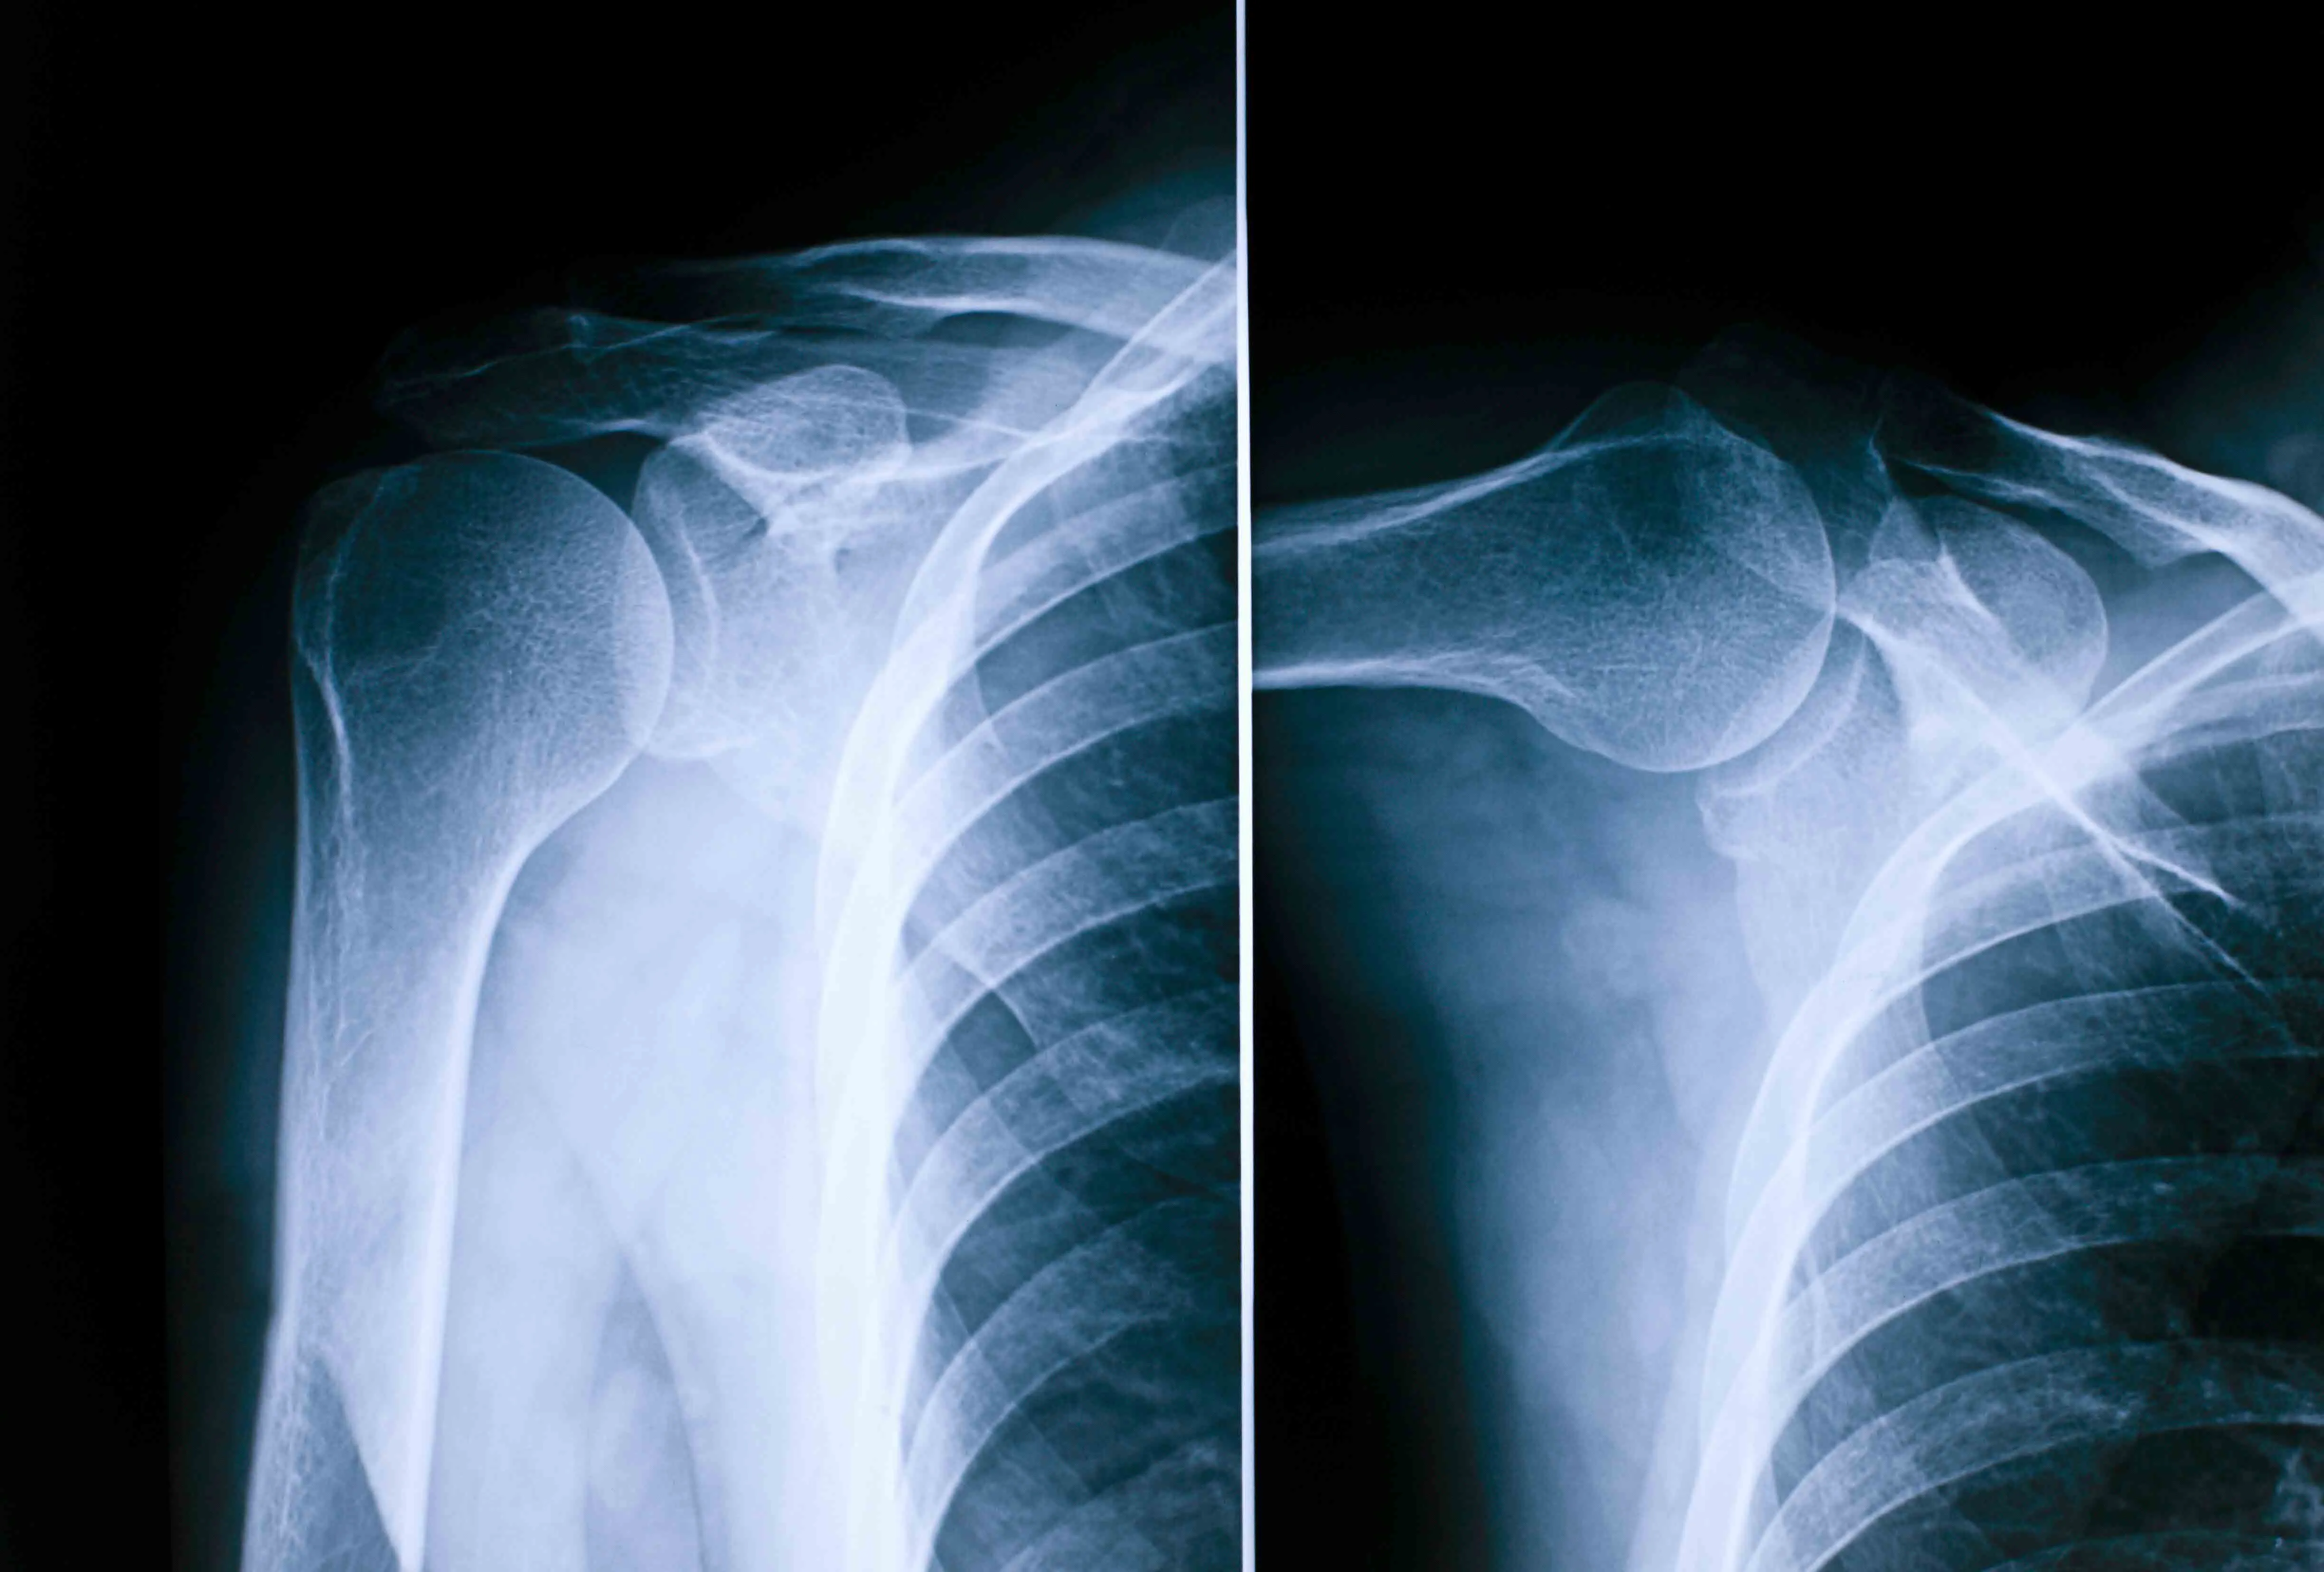

Raio-X Ombro

É um exame de rápida realização e indolor que utiliza raios Xpara a obtenção de uma imagem radiográfica do ombro.

Radiografia do ombro utilizada na Cintramédica para diagnóstico de lesões articulares, fraturas e doenças musculoesqueléticas.